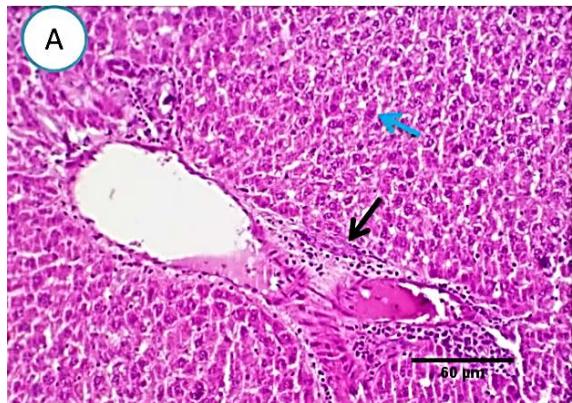

### c) Group3 (Methomyl pesticide)

Liver: Examined sections from liver of this group denoted moderate portal biliary proliferation, congestion of portal blood vessels, round cell infiltration, multifocal interstitial lymphocytic and macrophages aggregations replacing previous necrotic patches beside degenerative changes in a few hepatocytes. (Fig.4).

Fig. 3: Photo-micrograph from liver, group (2), showing, portal biliary proliferation (yellow arrow), congestions of portal blood vessels (blue arrow) and round cell infiltration beside degenerative changes in a few hepatocytes. Scale bars 120, 20 um.